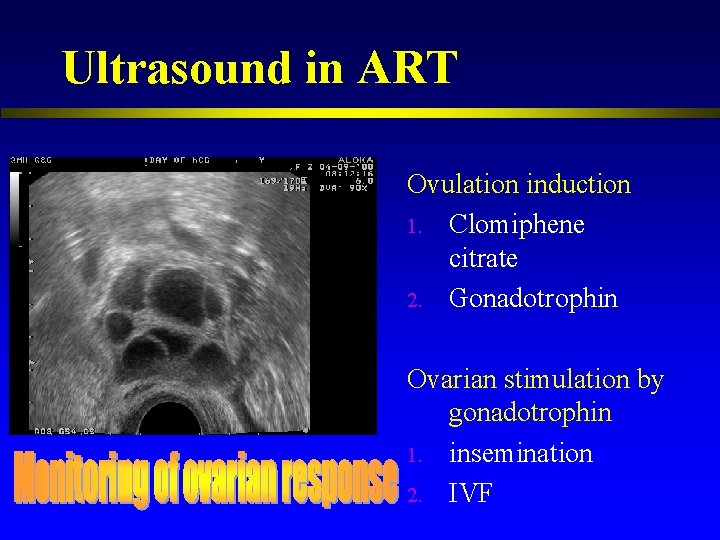

Ultrasound in reproduction 1. 2. Subfertility workup Assisted reproduction technique Ø Ø l Monitoring of ovarian response Timing of the procedure Oocyte retrieval / embryo transfer under ultrasound guidance Prediction of ovarian response and pregnancy Early pregnancy scanning

Ultrasound in ART Ovulation induction 1. Clomiphene citrate 2. Gonadotrophin Ovarian stimulation by gonadotrophin 1. insemination 2. IVF